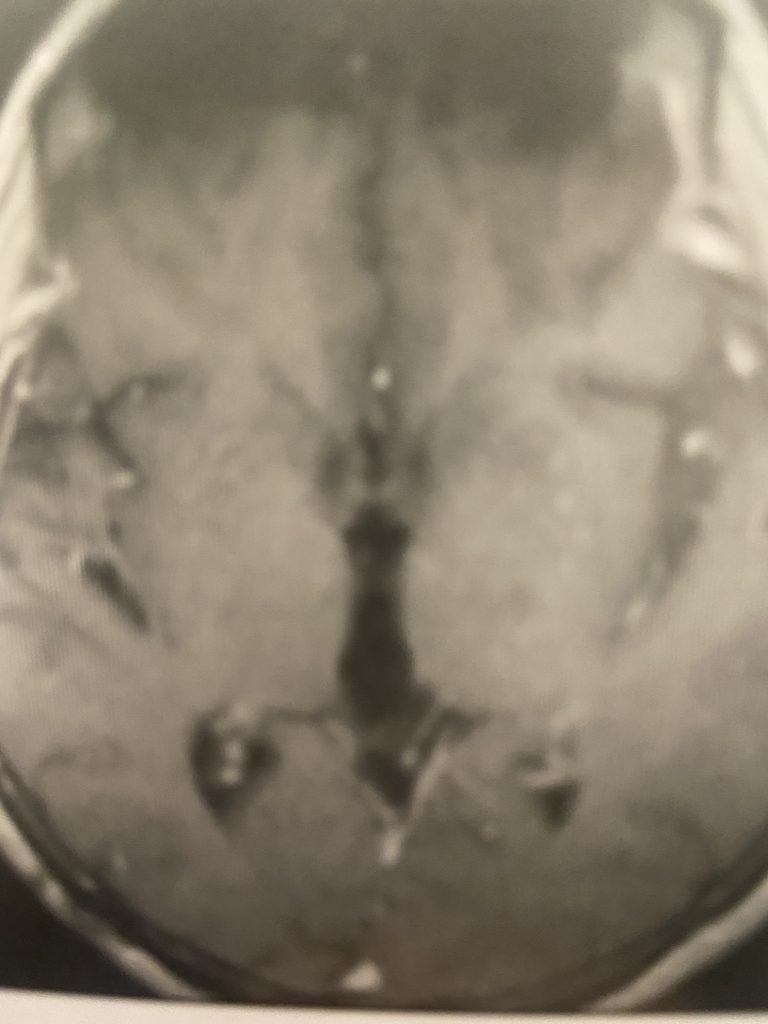

Figure 2: Images demonstrating the right occipital / transtentorial operative approach.

The traditional surgical approach to this region is the midline supracerebellar approach, performed with the patient in the seated position. We chose instead the right occipital / transtentorial approach. The major advantages of this alternative approach are (1) it is much easier technically for the surgeon, and (2) the risk of a serious air embolus is much lower. The major risk of surgery in the pineal region is injury to one of the large deep veins, which can result in a serious venous infarct.